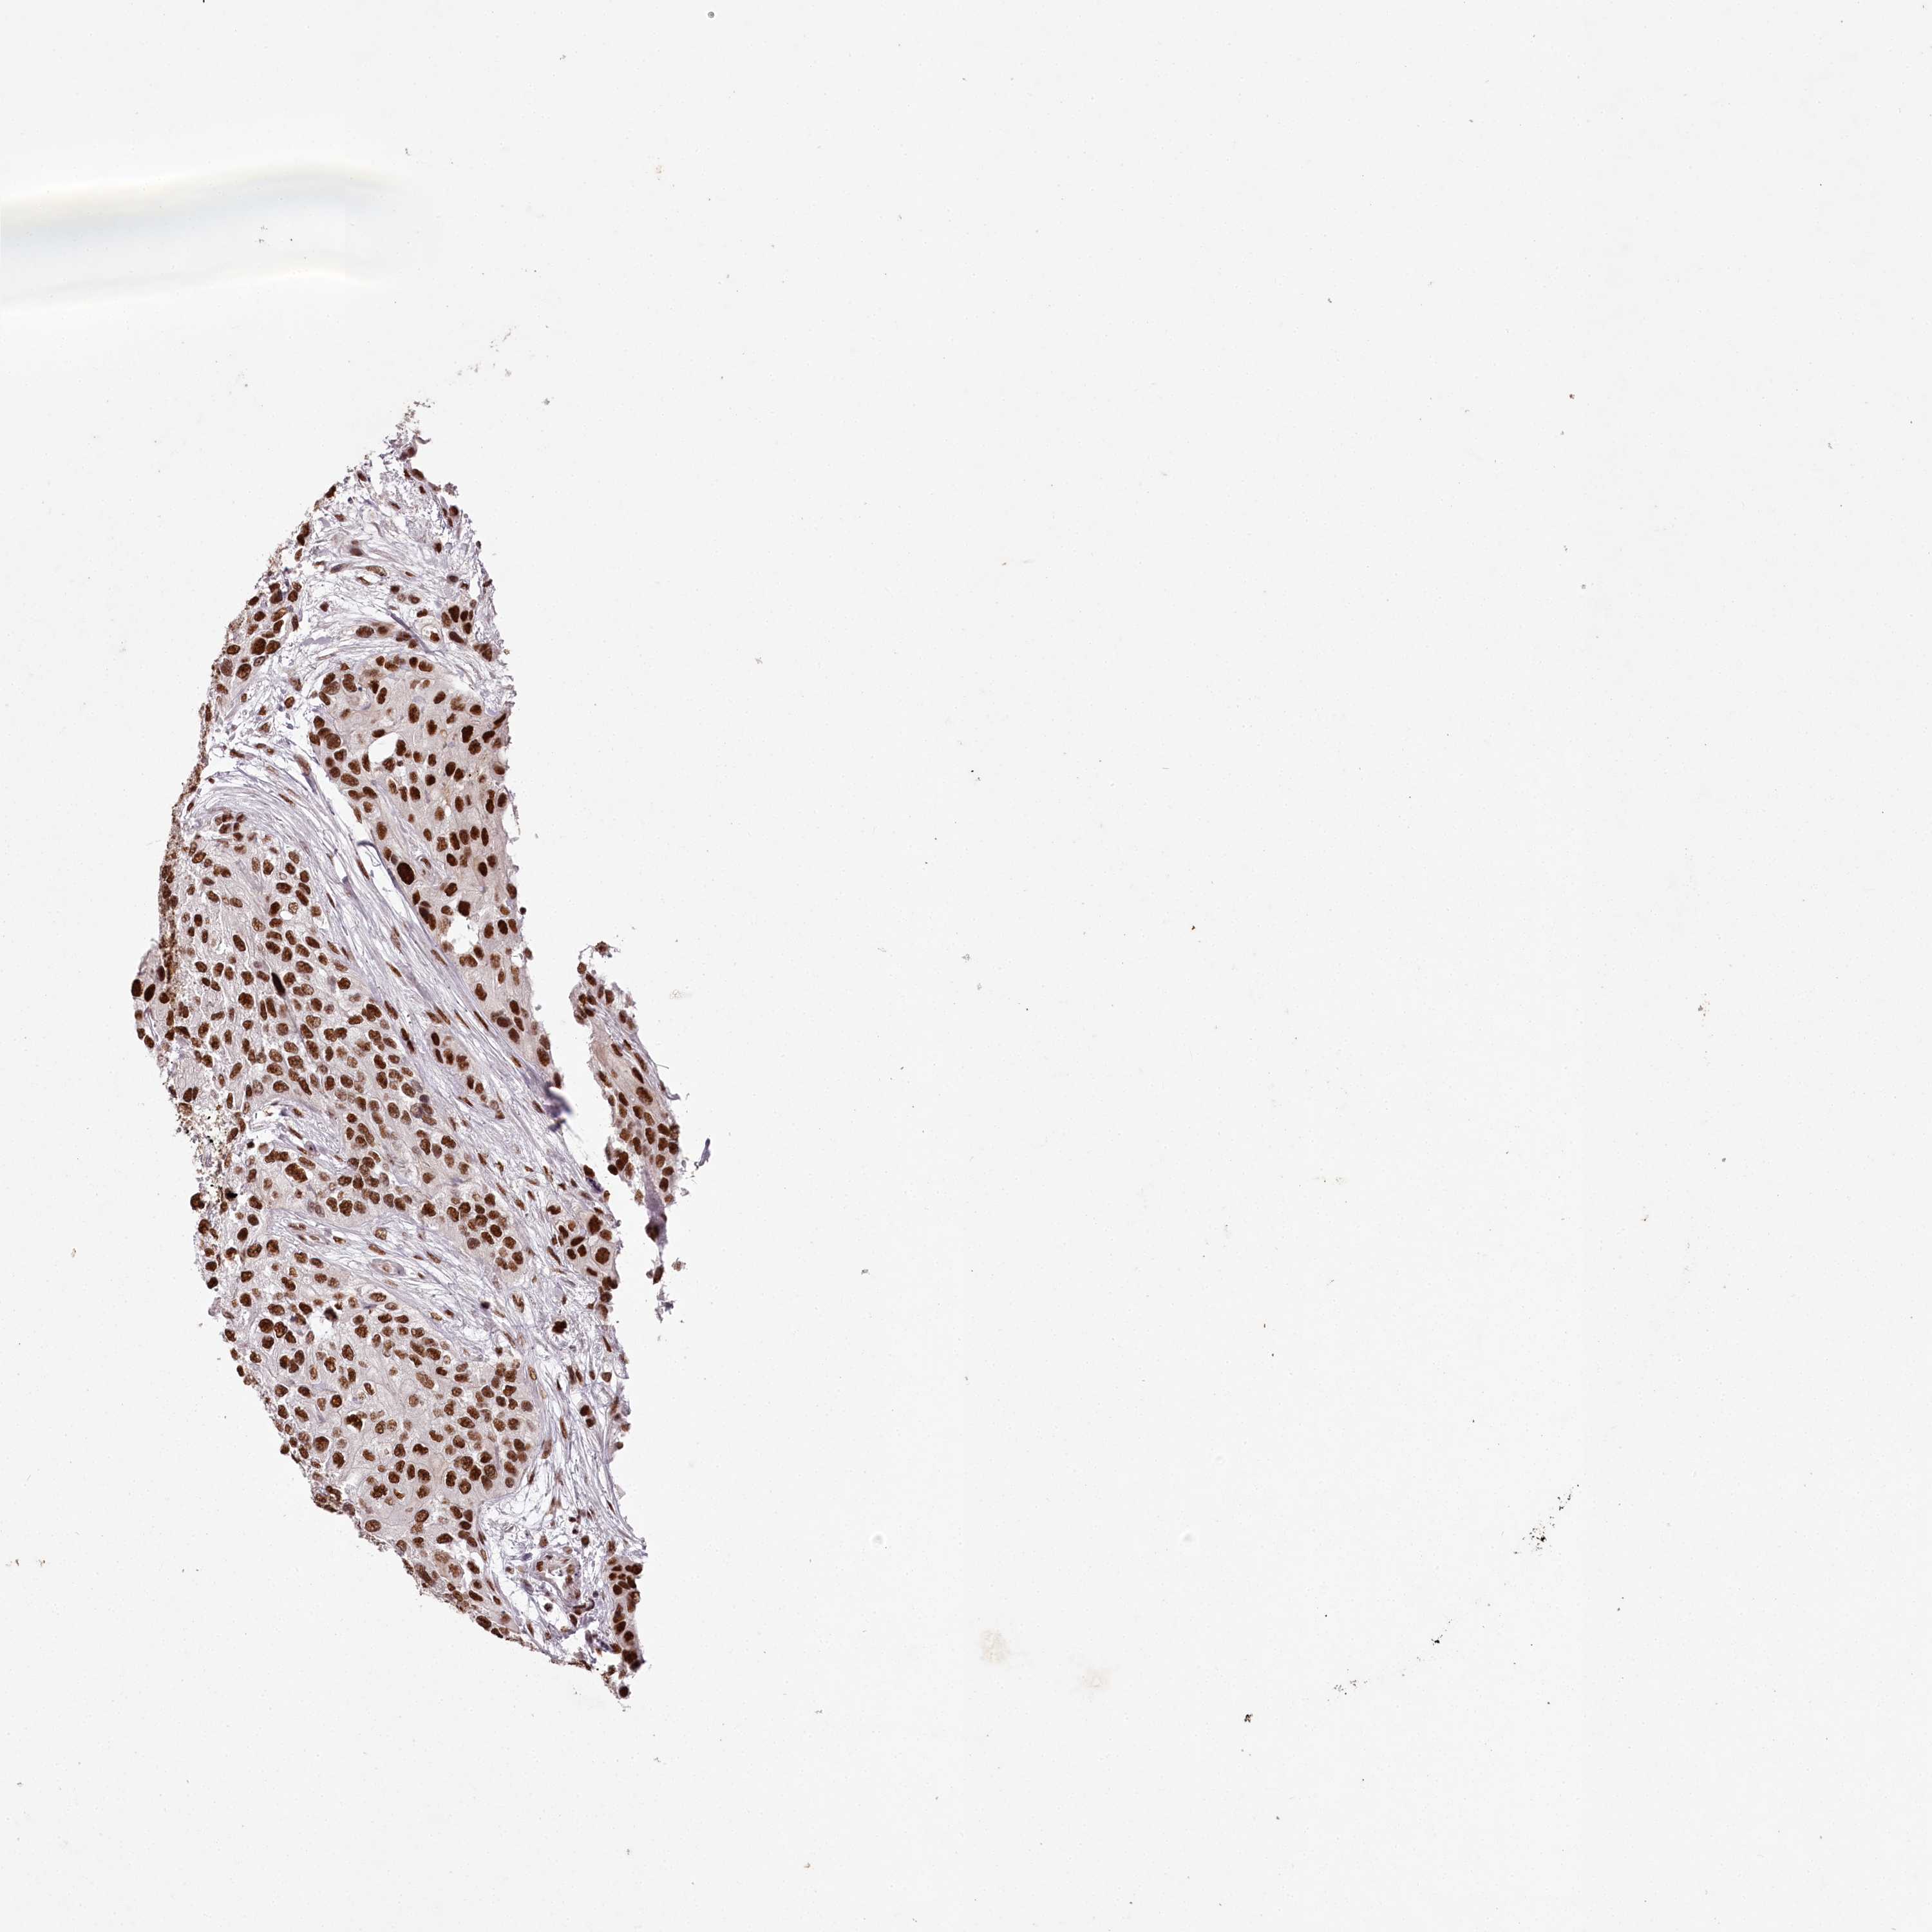

UROTHELIAL CANCER - Protein expressioni

A mouse-over function shows sample information and annotation data. Click on an image to view it in a full screen mode. Samples can be filtered based on level of antibody staining by selecting one or several of the following categories: high, medium, low and not detected. The assay and annotation is described here.

Note that samples used for immunohistochemistry by the Human Protein Atlas do not correspond to samples in the TCGA dataset.

Antibody stainingi

Antibody staining in the annotated cell types in the current human tissue is reported as not detected, low, medium, or high, based on conventional immunohistochemistry profiling in selected tissues. This score is based on the combination of the staining intensity and fraction of stained cells.

Each image is clickable and will lead to virtual microscopy that enables deeper exploration of all samples and also displays staining intensity scores, fraction scores and subcellular localization as well as patient and tissue information for each sample.

Antibody HPA038904

Staining

High

Medium

Low

Not detected

Intensity

Strong

Moderate

Weak

Negative

Quantity

>75%

75%-25%

<25%

None

Location

Nuclear

Cytoplasmic/membranous

Cytoplasmic/membranous,nuclear

Urothelial carcinoma, High grade

Urothelial carcinoma, Low grade